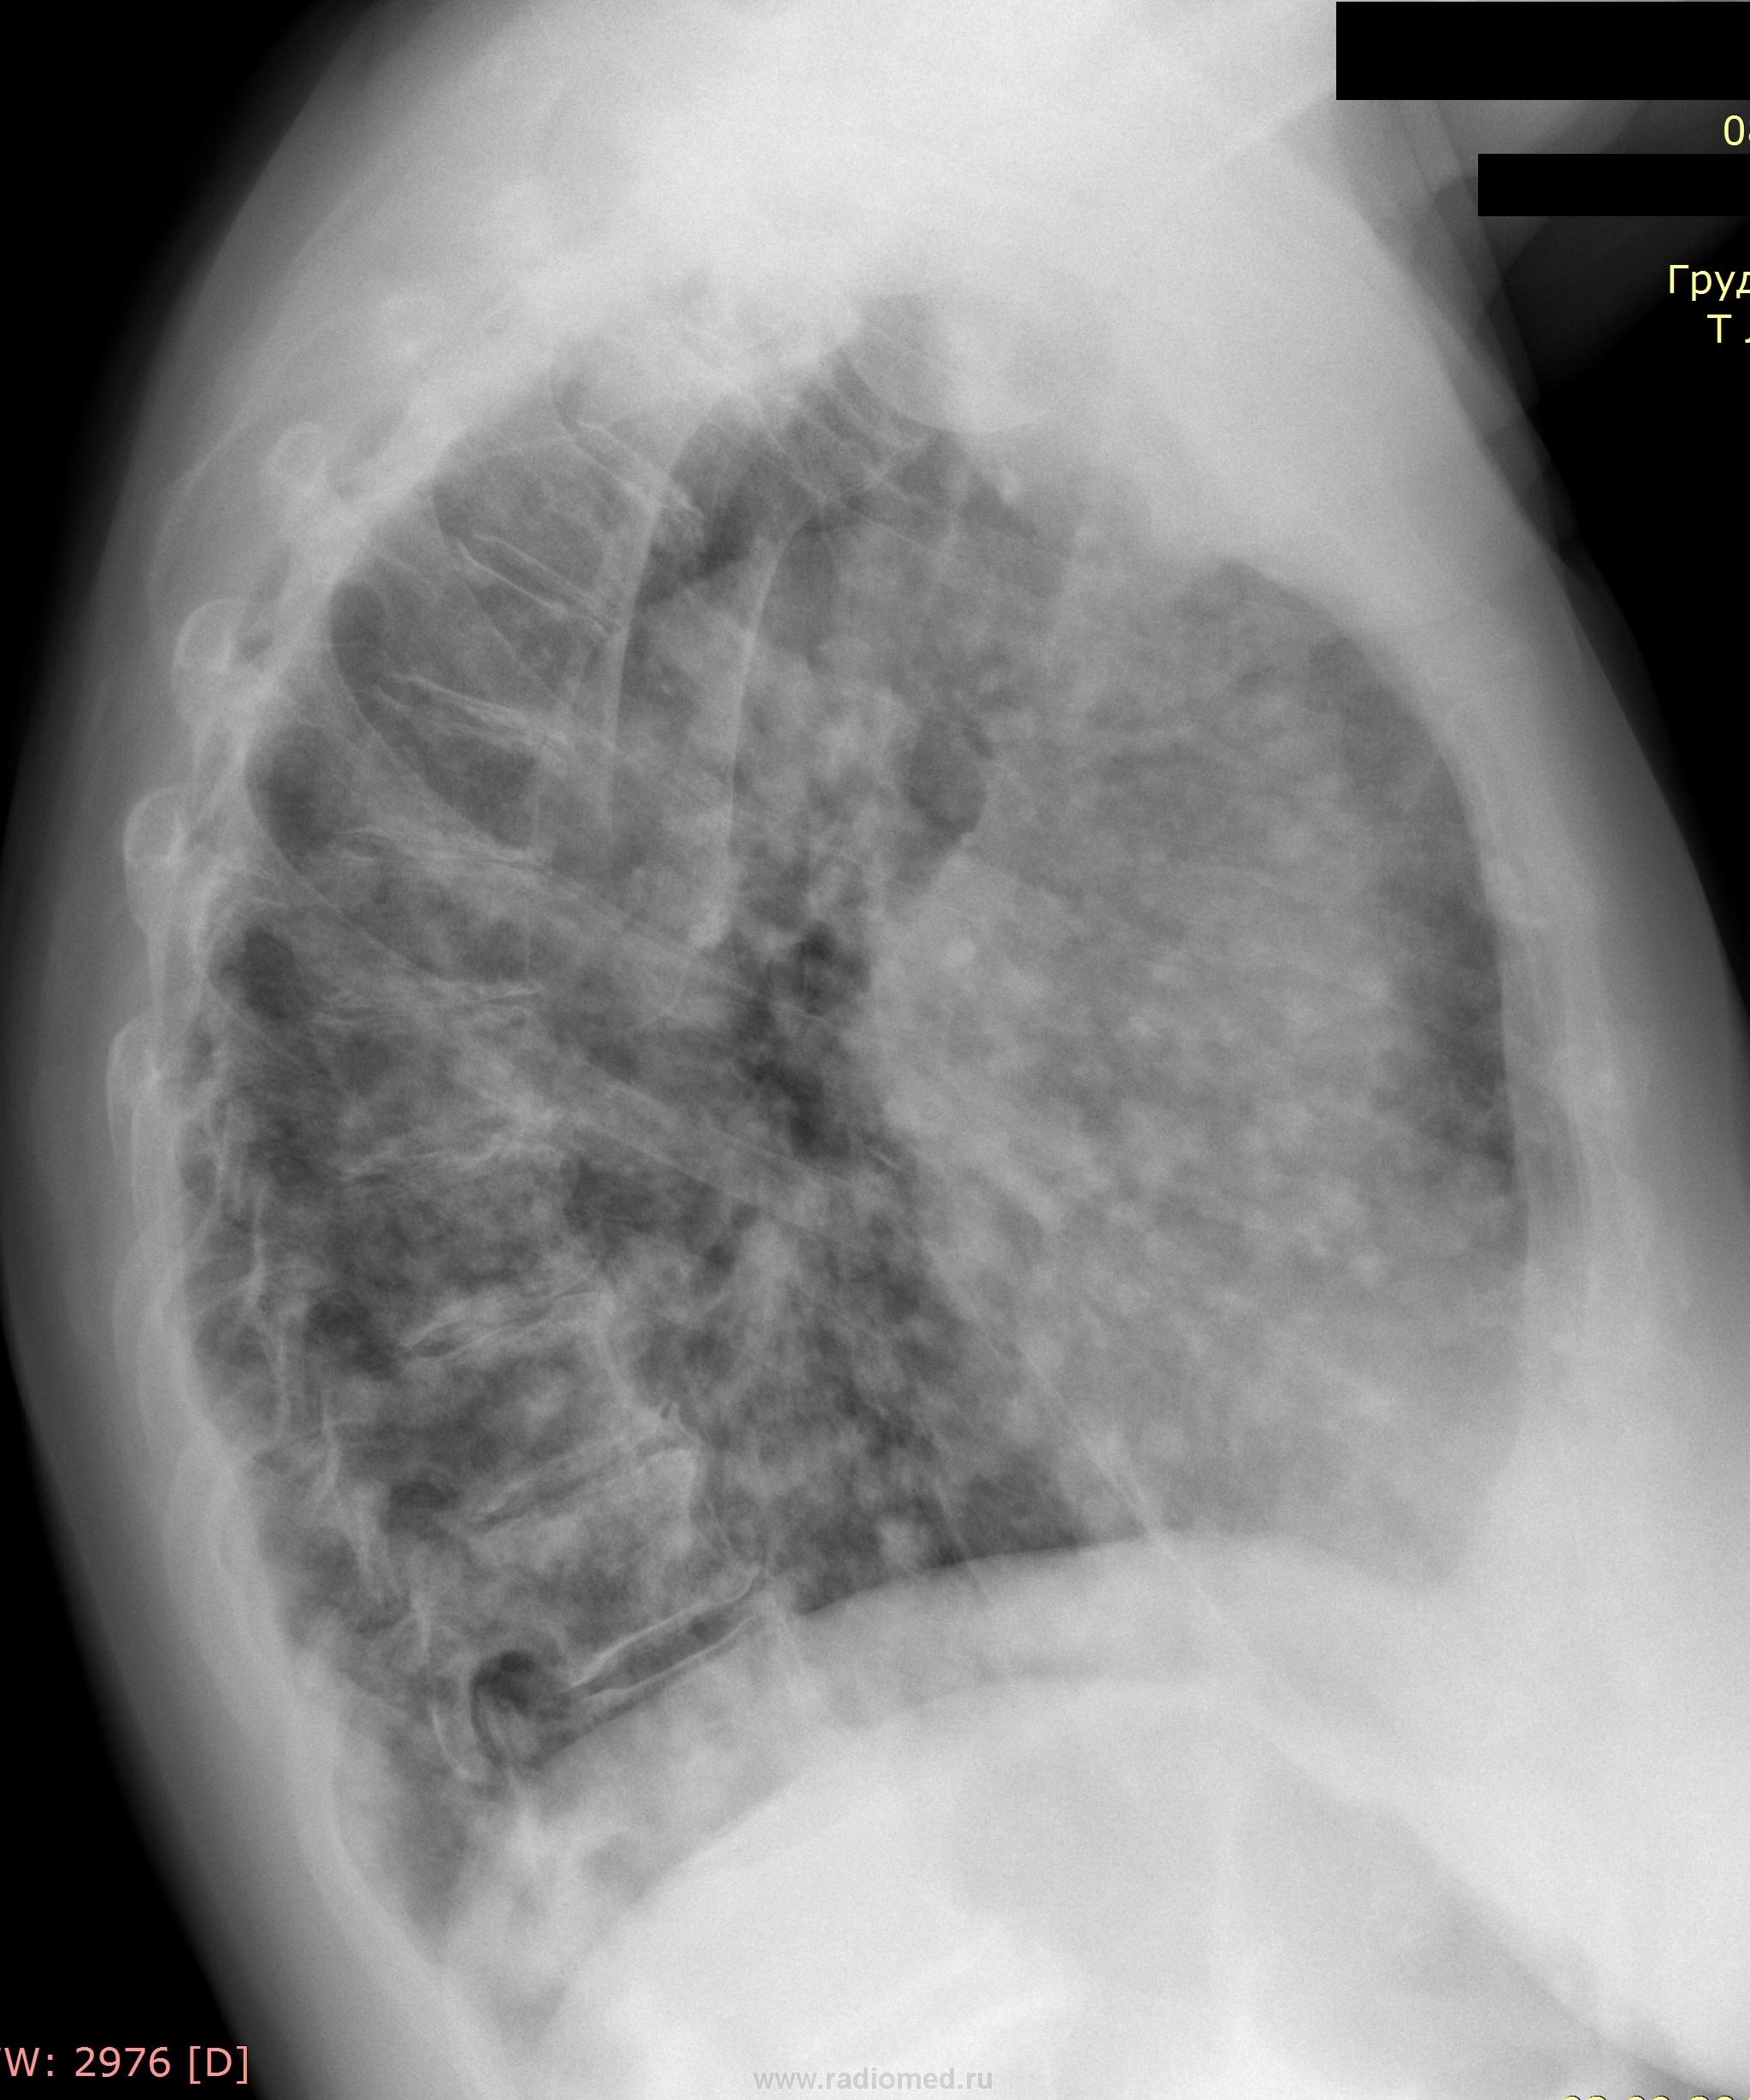

Пол пациента: Женский пол Тип патологии: Воспалительное заболевание неинфекционной природы Область исследования: Грудная клетка и верхние дыхательные пути Методы исследования: Rg живота. Т -норма. Кашель сухой. 78 лет. Ваше мнение коллеги. https://radiomed.ru/sites/default/files/styles/case_slider_image/public/user/7898/img-0007-00001.jpg?itok=m9l1moSu https://radiomed.ru/sites/default/files/styles/case_slider_image/public/user/7898/img-0008-00001.jpg?itok=H1qoB2GE ID:23236 Пнд, 17/09/2012 - 22:21 #1 Катенёв Валенти... Не на сайте Был на сайте: 7 лет 6 месяцев назад Зарегистрирован: 22.03.2008 - 22:15 Публикации: 54876 Синдром диссеминации. Крестец в боковой проекции не снимали? Пнд, 17/09/2012 - 22:27 #2 Nikolas Не на сайте Был на сайте: 2 месяцев 2 недели назад Зарегистрирован: 21.12.2010 - 20:37 Публикации: 4560 Почему вопрос о крестце? Интересно. Пнд, 17/09/2012 - 22:30 #3 Катенёв Валенти... Не на сайте Был на сайте: 7 лет 6 месяцев назад Зарегистрирован: 22.03.2008 - 22:15 Публикации: 54876 Структура по интенсивности разная, справа мал-мал плотнее. Да, и крестцовые отверстия справа, по сравнению с левой сторонй плохо дифференцируются. Пнд, 17/09/2012 - 22:53 #4 Mila85 Не на сайте Был на сайте: 3 года 7 месяцев назад Зарегистрирован: 15.03.2012 - 16:59 Публикации: 1790 Ужс, судя по скудной клинике скорее всего карциноматоз Пнд, 17/09/2012 - 22:54 #5 Almo Не на сайте Был на сайте: 4 дня 11 часов назад Зарегистрирован: 28.09.2008 - 18:50 Публикации: 8306 В первую очередь подумал бы о MTS поражении лёгких . Пнд, 17/09/2012 - 23:52 #6 И.Бондаренко Не на сайте Был на сайте: 1 час 45 минут назад Зарегистрирован: 13.09.2011 - 22:55 Публикации: 9214 +1 Втр, 18/09/2012 - 07:28 #7 Любовь С. Не на сайте Был на сайте: 9 лет 11 месяцев назад Зарегистрирован: 23.12.2010 - 01:58 Публикации: 2324 ФЭГДС. Первопричина может быть в желудке. В тазу затемнение справа выходит за контур крестца, скорее выпот в паравезикальном кармане. В легких мтс. "Предоставляя весь смысл и совершенство в распоряжение одного только Бога, вы избавляете себя от бездны хлопот." Джон Уитборн. Втр, 18/09/2012 - 18:41 #8 Наталия Васильевна Не на сайте Был на сайте: 6 лет 2 месяцев назад Зарегистрирован: 25.09.2011 - 09:02 Публикации: 754 Или БАР. Втр, 18/09/2012 - 19:24 #9 stovbav Не на сайте Был на сайте: 2 года 8 месяцев назад Зарегистрирован: 20.12.2009 - 17:28 Публикации: 7066 Наталия Васильевна wrote: Или БАР. Почему так? Интересен ваш ход мыслей, ведь картина 100% - метастазы.... Болезни ног: виды, симптомы, причины, профилактика и лечение Ср, 19/09/2012 - 09:46 #10 cupitur Не на сайте Был на сайте: 12 лет 4 месяцев назад Зарегистрирован: 19.09.2011 - 10:42 Публикации: 262 Мts Ср, 19/09/2012 - 19:01 #11 Наталия Васильевна Не на сайте Был на сайте: 6 лет 2 месяцев назад Зарегистрирован: 25.09.2011 - 09:02 Публикации: 754 stovbav wrote: Наталия Васильевна wrote: Или БАР. Почему так? Интересен ваш ход мыслей, ведь картина 100% - метастазы.... Было несколько случаев, при патологоанатомическом анализе -БАР, хотя первичные мысли были о множественных МТS, причем из желудка. Ср, 19/09/2012 - 19:04 #12 stovbav Не на сайте Был на сайте: 2 года 8 месяцев назад Зарегистрирован: 20.12.2009 - 17:28 Публикации: 7066 Наталия Васильевна wrote: stovbav wrote: Наталия Васильевна wrote: Или БАР. Почему так? Интересен ваш ход мыслей, ведь картина 100% - метастазы.... Было несколько случаев, при патологоанатомическом анализе -БАР, хотя первичные мысли были о множественных МТS, причем из желудка. Все возможно...сам с подобным не встречался..... Болезни ног: виды, симптомы, причины, профилактика и лечение

Синдром диссеминации.

Ужс, судя по скудной клинике скорее всего карциноматоз

В первую очередь подумал бы о MTS поражении лёгких .

ФЭГДС. Первопричина может быть в желудке. В тазу затемнение справа выходит за контур крестца, скорее выпот в паравезикальном кармане. В легких мтс.

Или БАР.

Почему так? Интересен ваш ход мыслей, ведь картина 100% - метастазы....

Мts

Было несколько случаев, при патологоанатомическом анализе -БАР, хотя первичные мысли были о множественных МТS, причем из желудка.